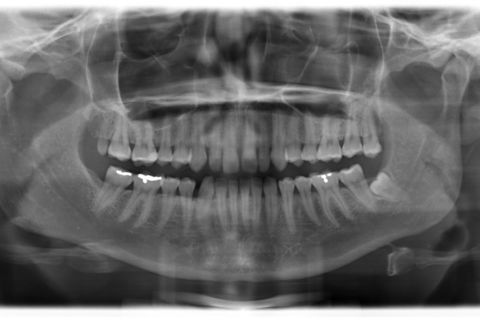

Pan

Paciente do sexo feminino, 29 anos.

Queixa principal: Espaços generalizados entre os dentes superiores (Diastemas), na qual a paciente relatava apresentar uma aparência infantil. Foi diagnosticado dentes com discrepância negativa de forma e tamanho, mas bem posicionados na arcada. Não sendo indicado fechamento de espaço através aparatologia ortodôntica.

Sugestão de Tratamento: 10 Laminados cerâmicos (Lentes de Contato Dentais), no arco superior contemplando os elementos dentários 15,14,13,12,11,21,22,23,24 e 25.